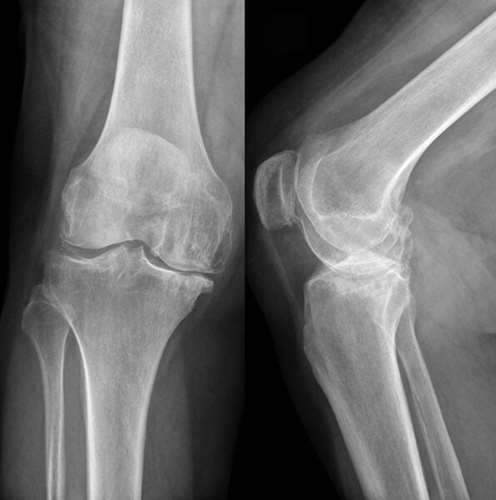

Запитання 59

СУГЛОБ СКЛАДНИЙ. УТВОРЕНИЙ СУГЛОБОВИМИ ПОВЕРХНЯМИ МЕДІАЛЬНОГО І ЛАТЕРАЛЬНОГО ВИРОСТКІВ, ЯКІ Є В ОБОХ КІСТКАХ, ЩО ЙОГО УТВОРЮЮТЬ. РОЗПІЗНАЙТЕ СУГЛОБ.

варіанти відповідей

КОЛІННИЙ С.

ЛІКТЬОВИЙ С.

ГОМІЛКОВО--СТОПНИЙ С.

ПРОМЕНЕВО-ЗАП'ЯСТКОВИЙ С.